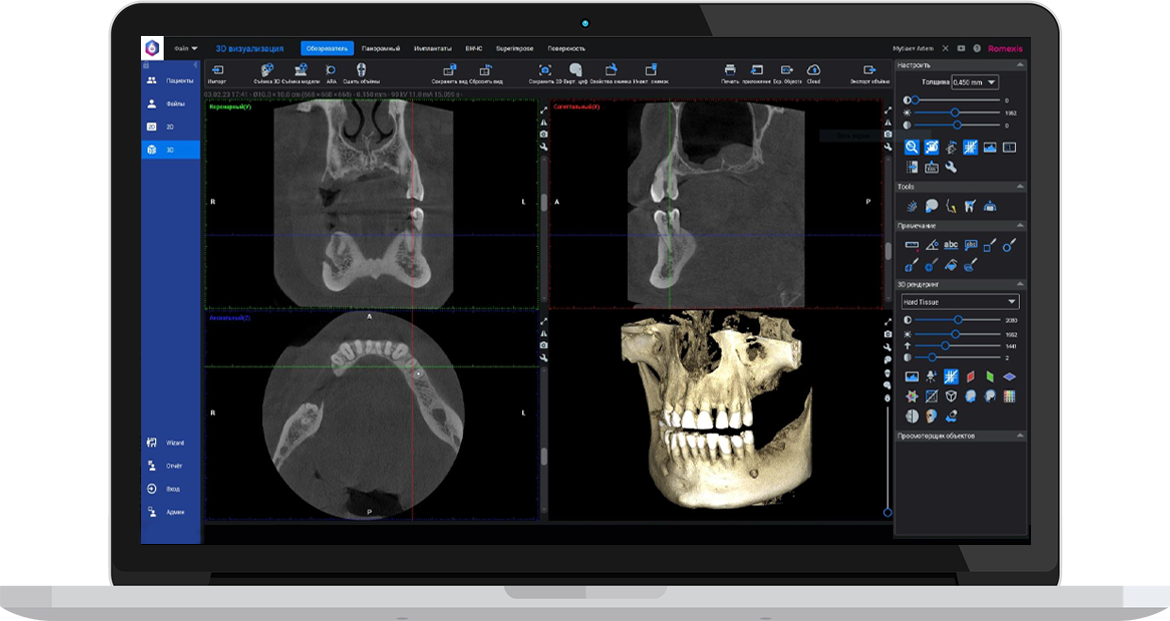

Ми використовуємо найсучасніше обладнання відомого виробника PLANMECA, що дозволяє отримувати високоякісні зображення за короткий час. Крім того, ми маємо власний сервер, на якому створюємо окрему скриньку для кожного лікаря, що забезпечує максимальну зручність та ефективність роботи.

3D цефалометричний аналіз є сучасною технологією, яка дозволяє отримувати точніші,

комплексніші та надійніші дані про зубну та скелетну структуру. Ця технологія може стати

великим кроком в перед для ортодонтів, які хочуть забезпечити найкраще можливе лікування

своїх пацієнтів.